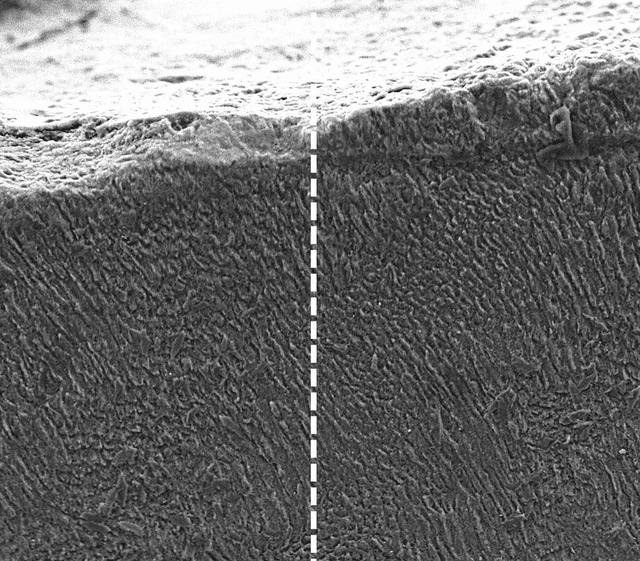

Antes (izq.) y después (der.) del tratamiento de queratina. Foto: King's College

Los expertos descubrieron que la queratina, una proteína presente en el cabello humano, la piel y uñas, forma una densa capa mineral que imita la estructura y función del esmalte natural, protegiendo los dientes y sellando los canales nerviosos expuestos que causan sensibilidad. En el experimento se usó la lana de oveja, cuya composición es muy similar al cabello humano.

En el estudio publicado en Advanced Healthcare Materials se descubrió que, al aplicar la proteína a la superficie dental, interactúa con los minerales presentes de forma natural en la saliva para crear una estructura cristalina similar al esmalte. Este base continúa atrayendo iones de calcio y fosfato de la saliva, allanando el camino para que con el tiempo crezca una capa similar al esmalte.